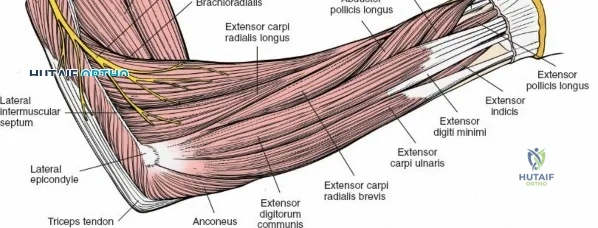

The anterior approach to the radius is an elegant example of utilizing true internervous planes to achieve deep exposure without denervating musculature. Distally, the internervous plane lies between the brachioradialis muscle (innervated by the radial nerve) and the flexor carpi radialis muscle (innervated by the median nerve). Proximally, the plane transitions to lie between the brachioradialis (radial nerve) and the pronator teres muscle (median nerve). Exploiting this plane allows the surgeon to mobilize the entire lateral muscular compartment (the "mobile wad" comprising the brachioradialis, extensor carpi radialis longus, and extensor carpi radialis brevis) away from the anterior flexor compartment.

Superficial Surgical Dissection and Internervous Plane

Incise the deep fascia of the forearm in line with the skin incision. The initial goal is to identify the medial border of the brachioradialis as it courses down the forearm. It is a common pitfall to search for this border too far laterally. At the level of the elbow, the brachioradialis is expansive and extends almost halfway across the anterior forearm. It is surprisingly easy to mistake the plane between the brachioradialis and the extensor carpi radialis longus for the correct intermuscular plane.